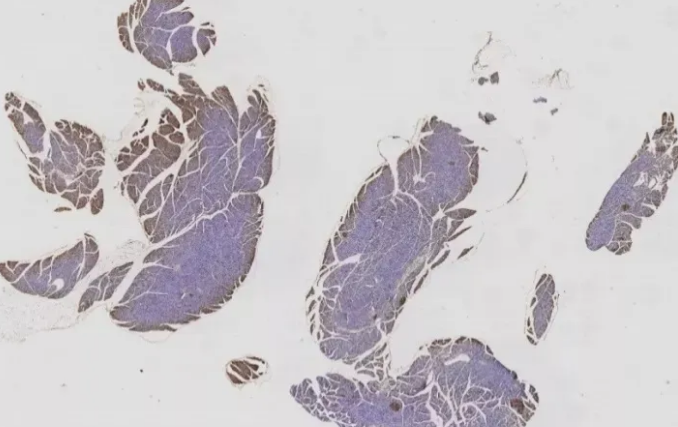

一、固定不充分

10%中性福爾馬林是目前應用最廣泛且效果較好的固定方式。組織塊太大,或固定時間太短,都會導致固定不充分。一般8-24h為宜,具體還需要經(jīng)過實際操作摸索確定。如圖1的這種情況,可適當延長固定時間到48h。

圖1 固定不充分